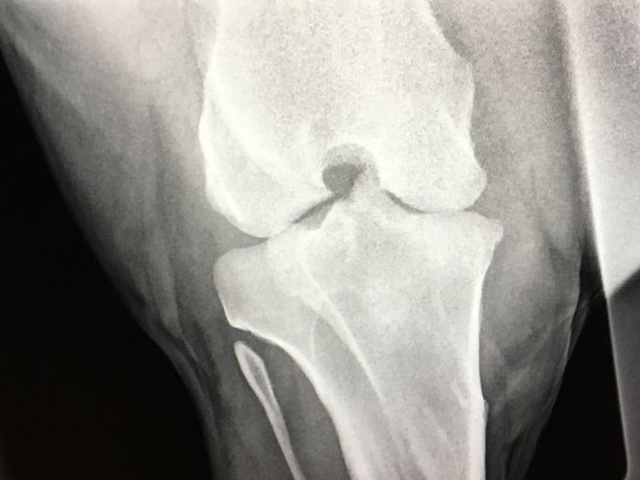

Røntgen

Jeg tilbyder røntgen af din hest med et af de nyeste digitale mobile systemer på markedet. Røntgen kan være en del af handels- eller forsikringsundersøgelsen eller relevant for at stille en diagnose ved haltheder. Har du ikke mulighed for at transportere din hest har jeg mulighed for at tage billederne hos dig, såfremt din stald opfylder nogle sikkerhedsmæssige krav mht. stråling.